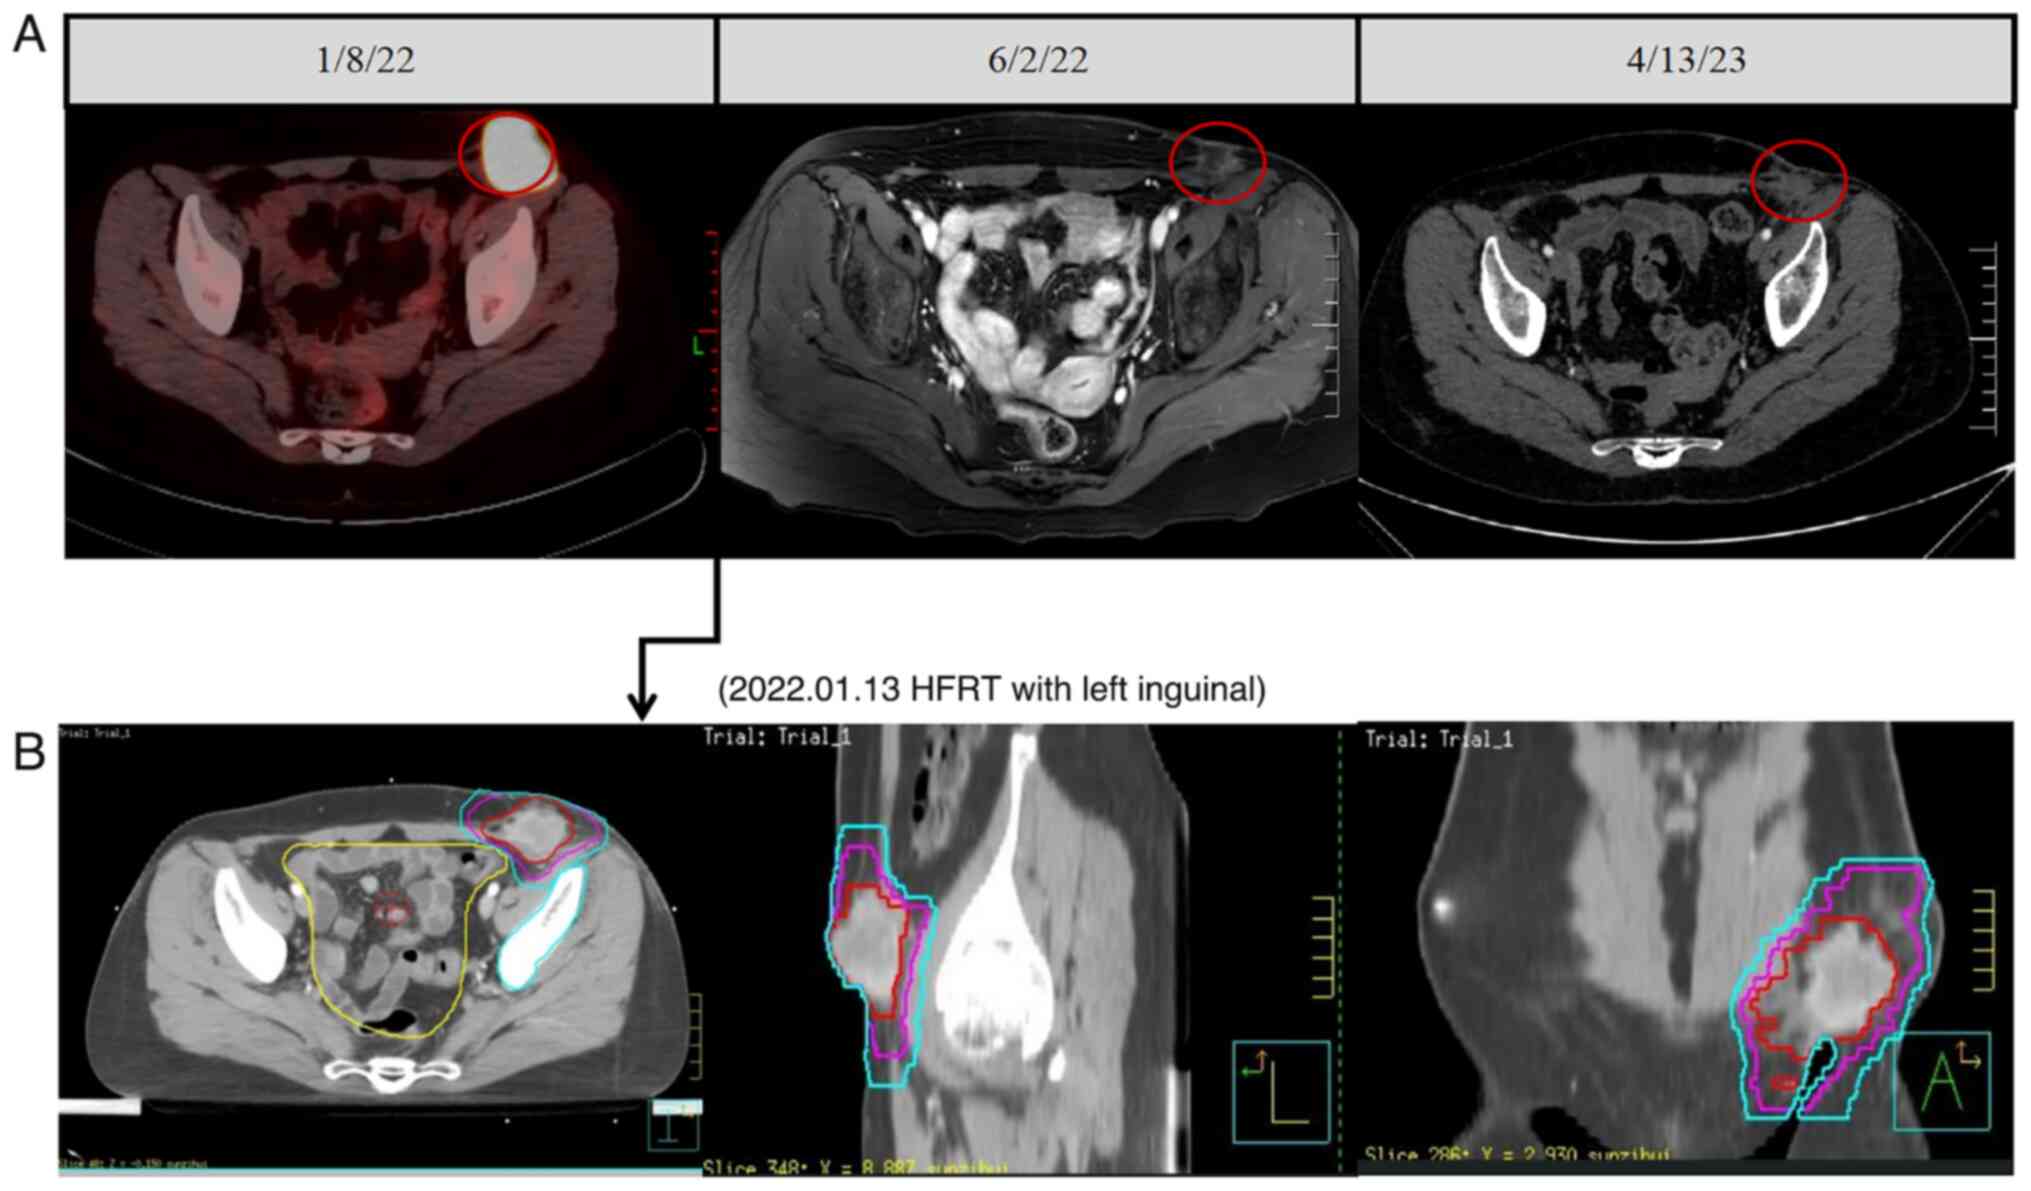

However, in January 2022, the patient consulted the Oncology Department of the Affiliated Hospital of Southwest Medical University (Luzhou, China) due to the persistent progression of the inguinal mass with pain and discomfort. PET/CT showed a soft tissue mass with increased glucose metabolism in the left inguinal region (diameter of ~48.9 mm) with a maximum standardized uptake value (SUVmax) of 17.5 (Fig. 2A). Multiple nodules were present in both lungs (the largest metastasis in the left lung tumor was 10.5 mm, and the largest in the right lung tumor was ~12.2 mm with a SUVmax of 2.9). After evaluation of the patient's condition in the Oncology Department, the patient underwent intensity-modulated radiation therapy for the left inguinal metastasis (3,414 cGy/7F) (Fig. 2B). Following radiotherapy for the left inguinal metastasis, the patient was treated with four cycles of pembrolizumab (200 mg, d0) and dacarbazine (385 mg, d1–5 po). During this period, owing to the increased and persistent lung metastases, the patient received single-fraction high-dose-rate brachytherapy, with a treatment dose of 49 Gy for the left lung metastases [D90 244 Gy by equivalent dose in 2-Gy fractions (EQD2)] (Fig. 3A) in March 2022 and 52 Gy for the right subpleural metastases (D90 269 Gy by EQD2) (Fig. 3B) 2 months later.

Figure 2.

Treatment and images of the inguinal lymph nodes. (A) Images of the inguinal lymph nodes. (B) CT simulation images of the inguinal lymph node radiotherapy planning. The red circles are the target lesions for radiotherapy. HFRT, hypofractionated radiotherapy.

After the lung metastatic lesion was treated with single-fraction high-dose-rate brachytherapy, the time of lung radiotherapy lesion (target lesion) control was 8 months (Fig. 3). The observation lesions (observation lesions 1, 2, 3 and 5) adjacent to the target lesion received lower doses of scattering (0.9–1.8 Gy), and the time of lung observation lesion control was 9 months (except for observation lesion 4 in the right lung, which received a radiation dose of 7.8 Gy) (Figs. 3 and S1). After receiving HFRT for the left inguinal mass after immunotherapy, the radiotherapy target area continued to shrink, with a gradual relief of pain and discomfort and a significant improvement in the quality of life of the patient. In February 2023, an MRI showed no enlargement of multiple small lymph nodes in the bilateral inguinal area. The inguinal mass had largely disappeared, and the inguinal mass was assessed as complete response (CR; 100% regression of the lesion with no new lesions is considered CR) to treatment. After 2 months, the examination showed that the left inguinal mass was still under control (Fig. 2A), and the inguinal mass was still assessed as CR. The inguinal mass remained rated as CR until the death of the patient. The clinical history of the patient and the course of treatment are summarized in Fig. 4.